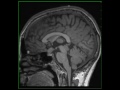

Neurofibromatosis Type 1

25-year-old female with a history of neurofibromatosis type 1 (NF-1). There are numerous poorly circumscribed FLAIR-hyperintense lesion in the basal ganglia as well as the dentate nuclei region bilaterally. There is nodular enlargement of the optic chiasm and prechiasmatic segment of the optic nerve on the left. The enlarged optic nerve contacts but remains distinct from the infindibulum of the pituitary gland, as is demonstrated on the postcontrast images. The findings are compatible with an optic pathway glioma in the setting of NF-1. The patient also had numerous subcutaneous neurofibromas in the suboccipital region (not demonstrated on these images). NF-1 is also known as von Recklinghausen disease, which is the most common phakomatosis. 50% of cases are due to new mutations while the other half are due to inherited autosomal dominant mutations. To make the clinical diagnosis, two or more of the following are required: > 6 cafe au lait spots, 2+ neurofibromas or one plexiform neurofibroma, optic nerve glioma, osseous lesions (ribbon ribs, gracile bones, multiple non-ossifying fibromas, etc), sphenoid wing dysplasia, 2+ iris hamartomas (Lisch nodules), axillary or inguinal freckling and primary relative with NF-1.